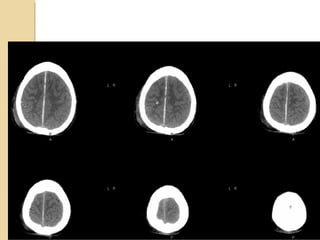

SUBFALCIAL HERNIATIONSUBFALCIAL HERNIATION Subfalcial:displacement of the cingulate gyrus under the free edge of the falx along with the pericallosal arteries. Can lead to anterior cerebral artery infarction

UNCAL HERNIATIONUNCAL HERNIATION Displacementof the medial temporal lobe through the tentorial notch Displacement of the midbrain Effacement of the suprasellar cistern Displacement of the contralateral cerebral peduncle against the tentorium Widening of the ipsilateral cerebello pontine angle Compression of the posterior cerebral artery